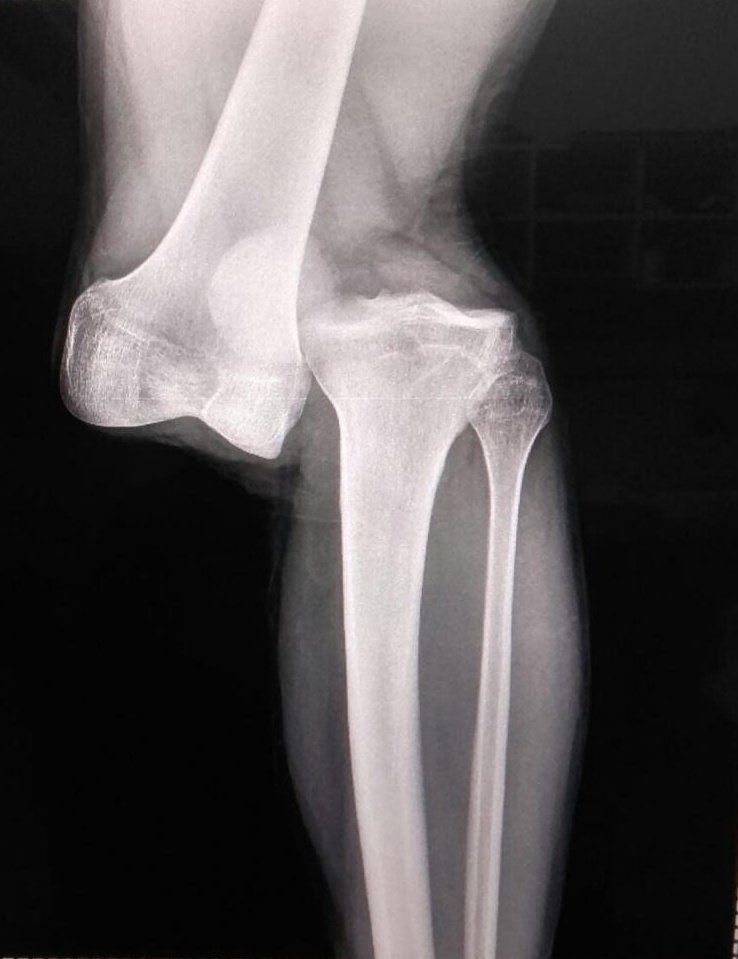

Acima, está a imagem do Raio-X de Luciano Sánchez, revelada pelo médico do Argentinos Juniors

O médico do Argentinos Juniors, Alejandro Ronconi, descreveu uma lesão como algo raro em sua experiência de 23 anos. Segundo ele, uma lesão é quase como uma separação do fêmur com a fíbula e evoluiu em uma ruptura dos ligamentos cruzados anterior e posterior. A gravidade do caso também envolve preocupação com os meniscos, que será necessário avaliar durante a cirurgia.

O prognóstico para a recuperação de Sánchez é de 10 a 12 meses, o que significa que o zagueiro passará um longo período fora dos gramados. A lesão é tão complexa que o jogador precisará passar por mais de uma intervenção cirúrgica para a sua reconstrução. A notícia abalou tanto os fãs do Argentinos Juniors quanto ao futebol em geral, já que a lesão foi chocante e impactante para todos os presentes no estádio e aqueles que acompanhavam o jogo pela televisão.